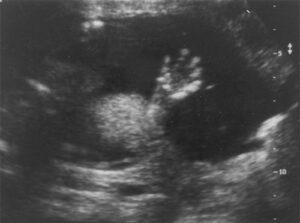

Explore the Biophysical Profile Score (BPS), a critical tool for assessing fetal well-being, developed to integrate real-time observations of the fetus and intrauterine environment. This course provides a comprehensive overview of the five components of the Biophysical Profile Score: fetal breathing movements, fetal movements, fetal tone, fetal heart rate reactivity, and amniotic fluid volume. Learn how these variables help assess fetal health, identify conditions such as hypoxia, and manage high-risk pregnancies. Understand the significance of the BPS in detecting complications like intrauterine growth restriction, congenital anomalies, and Rh sensitization, and how it influences perinatal mortality and morbidity. Ideal for obstetricians, sonographers, and healthcare professionals, this course enhances your ability to interpret the BPS for improved pregnancy outcomes.